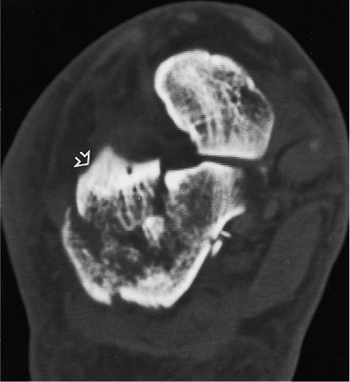

visualized on the foot films. The axial view demonstrates the position

of the tuberosity, the status of the medial wall, and the location of

the fracture(s) through the facet (Fig. 35.2).

Figure 35.2.

The axial (Harris) view demonstrates the primary fracture line, medial comminution, the fractures into the facet, and the varus angulation of the tuberosity. |